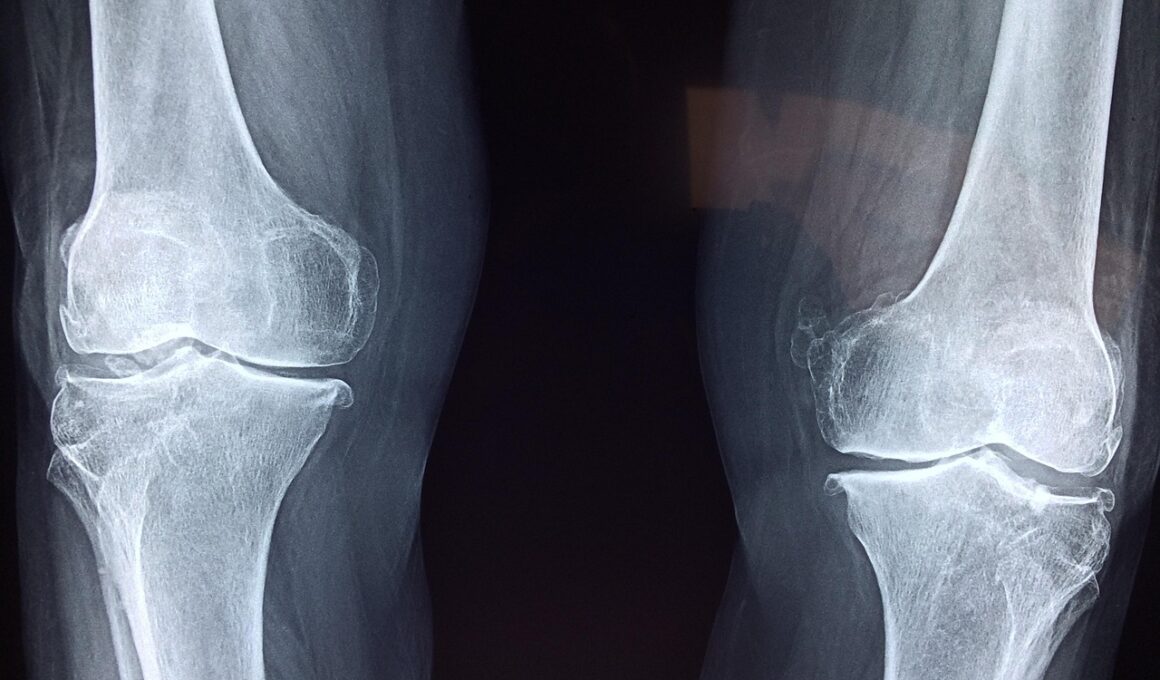

There are three primary types of cartilage present in joints: hyaline, elastic, and fibrocartilage. Each type serves distinct purposes and contributes differently to joint mechanics and flexibility. Hyaline cartilage, the most ubiquitous form, lines the ends of bones in synovial joints and reduces friction. During athletic movements, this cartilage helps absorb shocks, thereby preventing bone-on-bone contact and injury. Elastic cartilage, found in structures such as the outer ear, provides resilience and shape retention under pressure. While not commonly associated with joints, its properties are essential for certain athletic movements. Fibrocartilage, on the other hand, is found in high-stress areas like the menisci of the knee. It enhances joint stability and absorption of compressive forces. Understanding these three types is crucial for athletes, as it informs training choices. Targeting specific joint areas for conditioning can promote healthy cartilage, ensuring optimal function amidst physical demands. Athletes should recognize the importance of these cartilage types during training sessions and rehabilitation practices. Proper knowledge can thus drive informed decisions, fostering longevity in their athletic journeys as they strive for flexibility and performance.